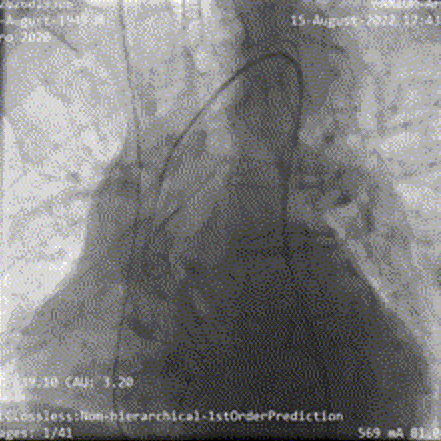

术前行冠状动脉造影提示左右冠状动脉未见有意义狭窄;

左冠造影